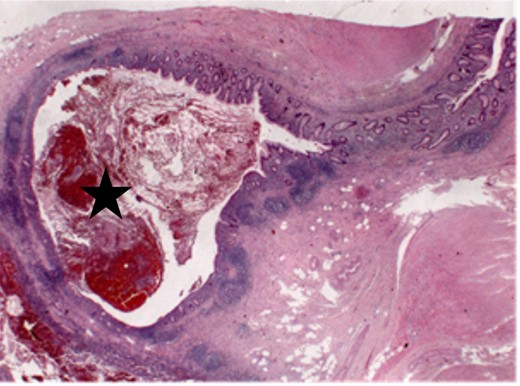

Three months later, the patient had exacerbation of the right lower quadrant pain. At this time, the pain was accompanied by fever and diarrhea appearing 4 days ago. Leukocyte count was still normal; CRP was slightly elevated (3.5 mg/dl). Repeated CT scan showed an increase in wall thickness of the vermiform appendix with mild surrounding reaction according to acute signs of inflammatory disease. A diagnostic laparoscopy with cholecystectomy and appendectomy was performed using standard four-port position for laparoscopic cholecystectomy [7] with only one additional incision (10-mm port) in the left lower quadrant for appendectomy. Intraoperatively, the appendix was suspicious and thickened. Pathologic analysis demonstrated one small appendiceal diverticula with inflammation (Fig. 1). The gallbladder showed a small tubular adenoma with low-grade dysplasia (Figs 2 and 3). The patient recovered well and was discharged 3 days later.